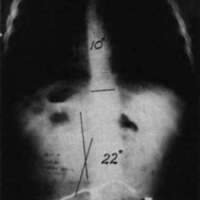

Figure 7. The diagrams on the left illustrate the similarity between the spinal column in the case of an uncontrolled pelvis and the slender column pin-jointed (free to tilt) at its lower end. The two diagrams on the right illustrate the similarity between the controlled pelvic case and the built-in base end condition.To fully appreciate the strength of this scheme in practice, compare the two x-rays in Fig. 8a and Fig. 8b. Fig. 8a is the x-ray taken just before the pelvic leveling procedure was performed and Fig. 8b is the x-ray taken a few minutes later, after the pelvic leveling procedure was performed. The Cobb angle is reduced from 36 degrees to 20 degrees by this quick procedure, which is normally performed as a routine part of positioning the child in the sitting support orthosis. These x-rays are of a boy with Duchenne Muscular Dystrophy; he was not wearing a corset.

Figure 8a. An x-ray taken just before the pelvic leveling procedure was performed.Figure 8b. The x-ray taken a few minutes later after the procedure.